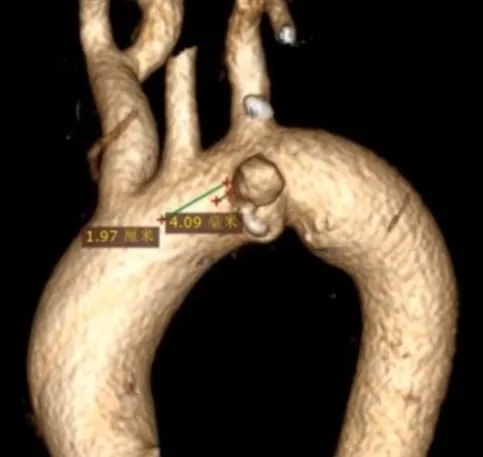

术前检查与评估

增强CTA显示,主动脉弓前壁假性动脉瘤深约2.23cm,基底宽约3.34cm。瘤体已累及左侧锁骨下动脉,且距左颈总动脉仅约4mm,距无名动脉约19.7mm。检查结果表明,该病例需要将覆膜区放置在无名动脉后,同时重建左锁骨下动脉和左颈总动脉,以恢复正常的血管通路,避免脑部供血不足等严重并发症的发生。

术前CTA

该病例胸主动脉瘤累及左颈总动脉根部位置的主动脉前壁,左锁骨下动脉与左颈总动脉距离仅4mm,如何在TEVAR术中有效进行LCCA+LSA原位重建是一大挑战。